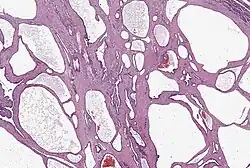

Pankreastumorzellen können Ähnlichkeit mit Zellen der Gänge (duktal), der Azini und Langerhans-Inseln aufweisen, aber auch gemischten Charakter haben.[22] In der Regel richten sich die Pathologen nach der WHO-Klassifikation bösartiger Tumoren, derzeit in der Ausgabe von 2019.[23] Die meisten bösartigen Tumoren (Malignome) werden danach als Varianten des duktalen Adenokarzinoms bezeichnet, eingestuft von hochdifferenziert bis undifferenziert.

Bei den Adenokarzinomen kann man im Mikroskop je nach ihrem Entartungsgrad noch schleimgefüllte Drüsenschläuche mit Zylinderepithel erkennen („duktaler Typ“). Die Nervenscheiden sind fast immer tumorinfiltriert. Charakteristisch ist außerdem eine Verdichtung des umgebenden Bindegewebes („desmoplastische Reaktion“), die in den bildgebenden Verfahren schlecht vom eigentlichen Tumor zu unterscheiden ist. „In der aktuellen WHO-Klassifikation werden die seltenen, prognostisch relevanten Subtypen wie das hochmaligne adenosquamöse Karzinom oder das niedrigmaligne Kolloidkarzinom [(muzinöse nichtzystische Karzinom, mikroskopisch „Schleimseen“)] deutlich untereinander und vom duktalen Adenokarzinom […] abgegrenzt“.[25]